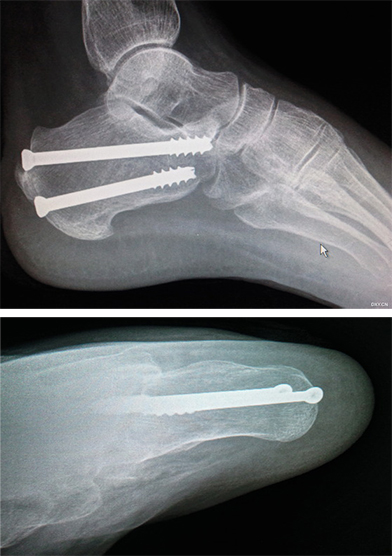

跟骨骨折(空心钉固定)

患者,女,76岁,跟骨骨折1小时入院,考虑手术风险患者起先不愿手术,石膏托外固定,2周后在我院医护人员的再三劝说,答应微创。考虑到患者年纪已经76岁,体质差,跟骨钢板固定切口大,伤口延迟愈合或不愈合可能,主刀王雷医师决定空心钉固定跟骨骨折。

手术在透视下经皮用斯氏针闭合撬拨复位,空心钉内固定,术程顺利,术后外观及X线: